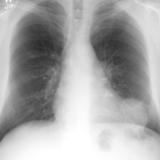

Normal pericardium